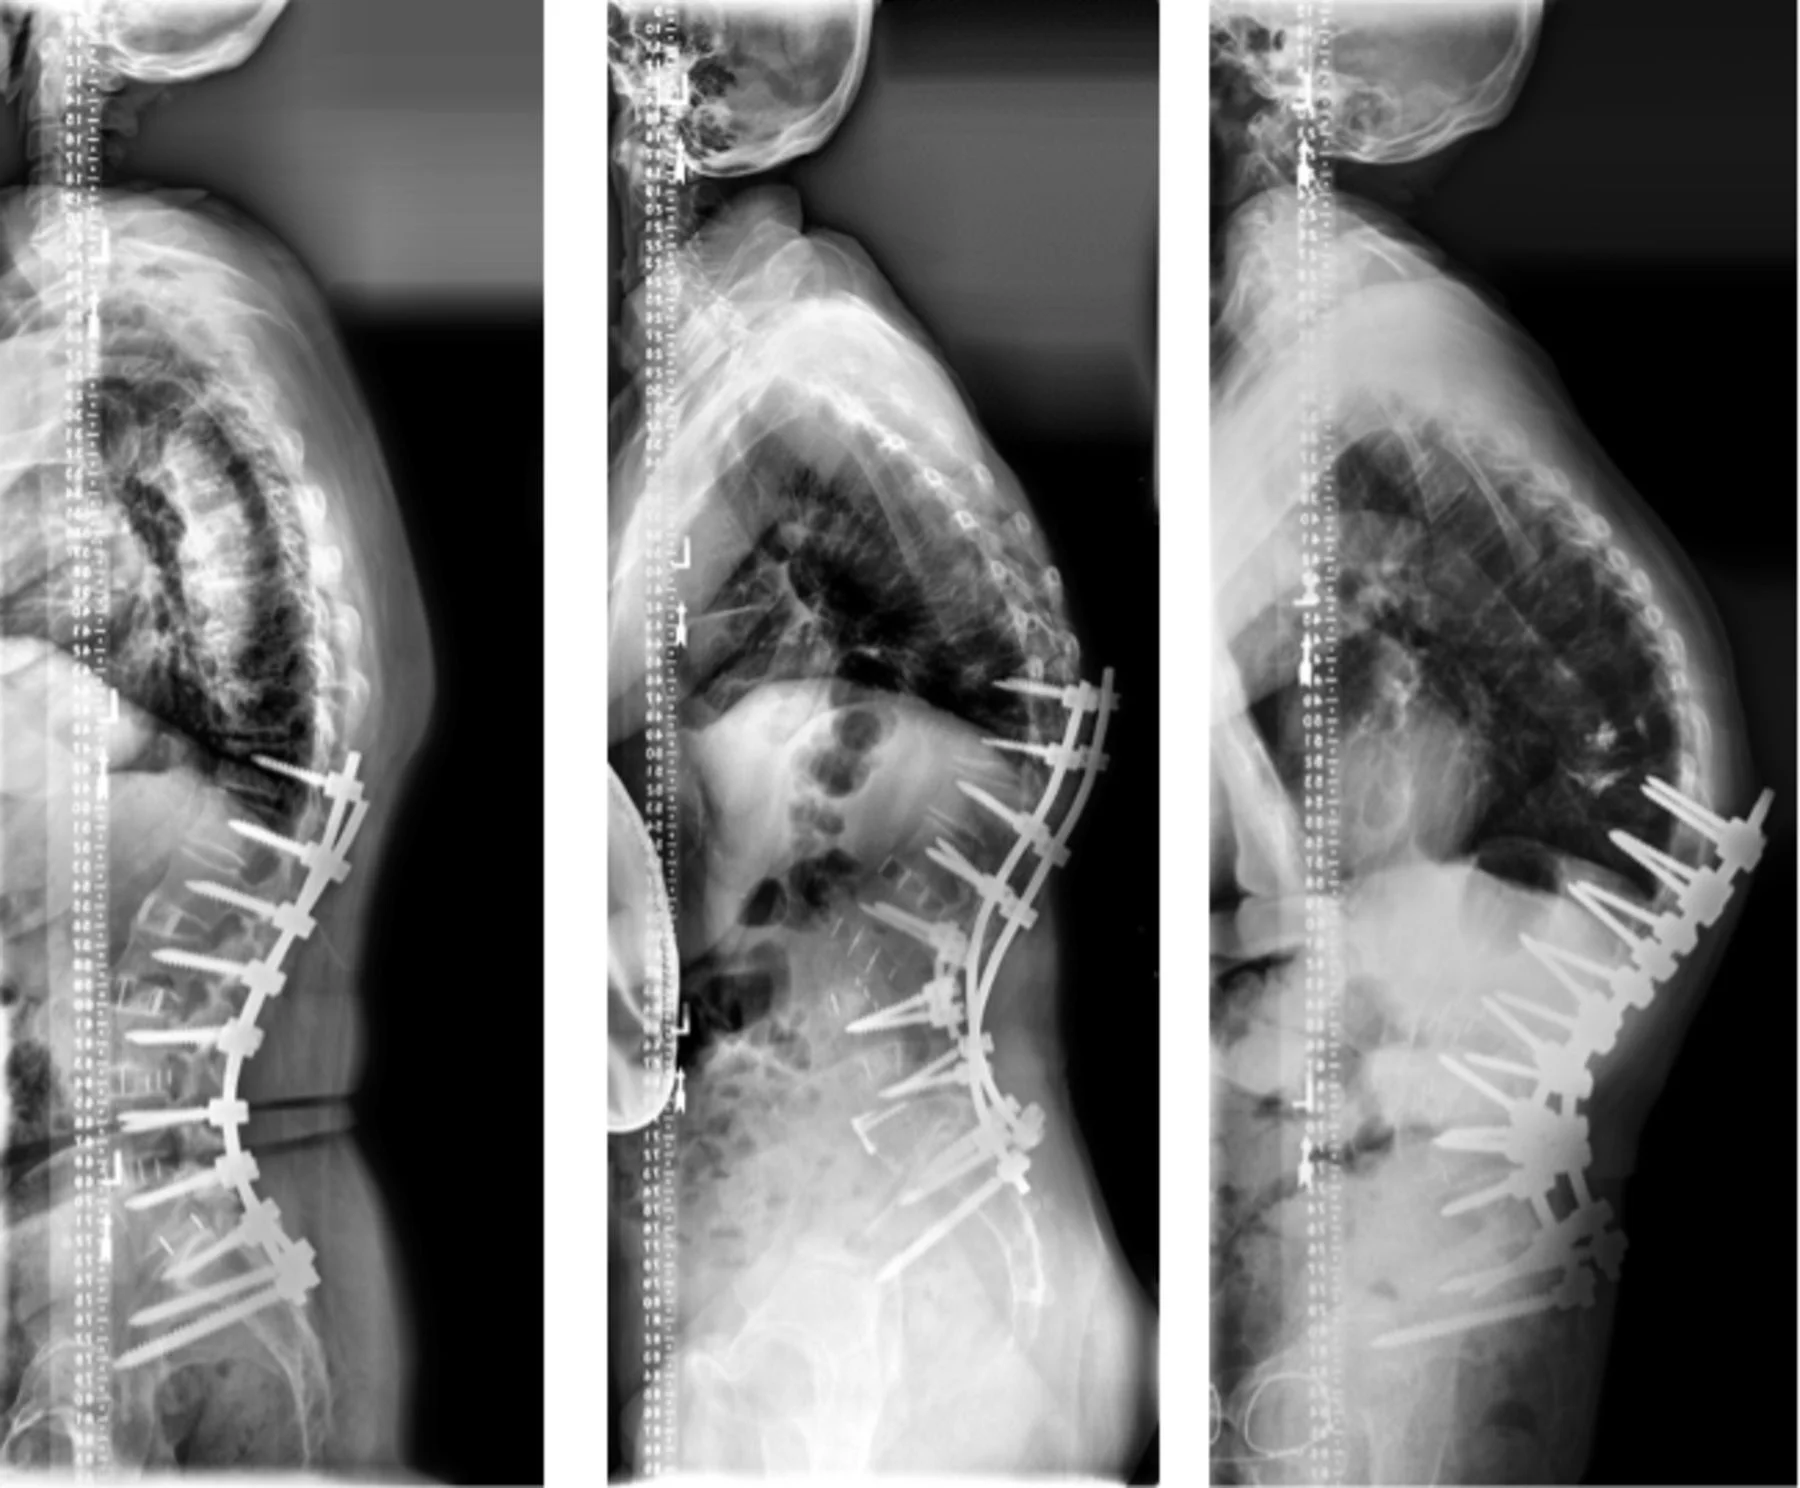

Κυφωτική παραμόρφωση μετά σπονδυλοδεσία

Η κυφωτική παραμόρφωση μετά σπονδυλοδεσία (Proximal Junctional Kyphosis/PJK) είναι μία σχετικά συχνή επιπλοκή μετά από μεγάλες σπονδυλοδεσίες με υλικά, ιδιαίτερα σε επεμβάσεις διόρθωσης σκολίωσης, κύφωσης ή εκφυλιστικής παραμόρφωσης σε ενηλίκους.

Ακτινολογικά, η PJK ορίζεται συνήθως ως γωνία κύφωσης > 10° μεταξύ της κάτω επιφάνειας του σπονδύλου (inferior endplate) στο άνω όριο της σπονδυλοδεσίας και της άνω επιφάνειας (superior endplate) του δεύτερου υπερκείμενου της σπονδυλοδεσίας σπονδύλου, ή αύξηση ≥ 10° σε σχέση με τις προεγχειρητικές μετρήσεις.

Πώς γίνεται η διάγνωση & πώς μετράμε την PJK (ακτινολογικά κριτήρια);

Η διάγνωση της PJK βασίζεται στην κλινική εξέταση και ειδικό ακτινολογικό έλεγχο, κυρίως με όρθιες ακτινογραφίες ολόκληρης της σπονδυλικής στήλης.

Τυπικό κριτήριο PJK είναι:

-

Γωνία κύφωσης > 10° μεταξύ:

- της κάτω επιφάνειας του σπονδύλου (inferior endplate) στο άνω όριο της σπονδυλοδεσίας και

- της άνω επιφάνειας (superior endplate) του δεύτερου υπερκείμενου της σπονδυλοδεσίας σπονδύλου,

- και/ή αύξηση ≥ 10° σε σχέση με την προεγχειρητική μέτρηση.

Συμπληρωματικά εργαλεία:

- Πλάγιες ολοσωματικές ακτινογραφίες για αξιολόγηση της οβελιαίας ισορροπίας (SVA, LL κ.λπ.).

- CT ή MRI αν υπάρχει υποψία κατάγματος, αστοχίας υλικών, αποτυχίας της αρθροδεσίας ή πίεσης επί των νευρολογικών δομών.